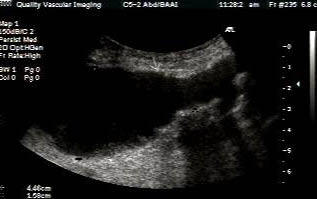

Patients should fast overnight to eliminate excess bowel gas. Scan the patient supine and lateral decubitus. Scan the Aorta in sagittal and transverse including grayscale, color doppler and spectral waveform analysis. Document proximal, mid and distal aorta and bilateral Iliac arteries including anteroposterior measurements.

Aneurysms >3 cm in size gradually enlarge at rate of 0.2 -0.8 mm/year. There is a high risk of rupture once the aneurysm reaches 5 cm. A 7-cm AAA has a 19-32% rate of rupture per year.